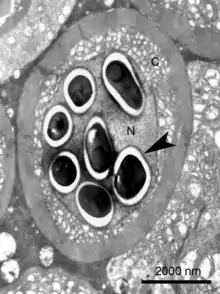

| Transmission electron micrograph of an Enterospora nucleophila-infected rodlet cell harbouring spores within its nucleus (N). No stages are visible in the cytoplasm (C) | |

Enterospora nucleophila is a microsporidian infecting the gilt-head bream (Sparus aurata). It develops primarily within the nuclei of rodlet cells and enterocytes, at the intestinal epithelium. It can also be found in cytoplasmic position within other cell types, including phagocytes, at subepithelial layers. It is the causative agent of emaciative microsporidiosis of gilthead sea bream, a chronic condition manifested as a severe growth arrestment, normally accompanied by trickling mortality.